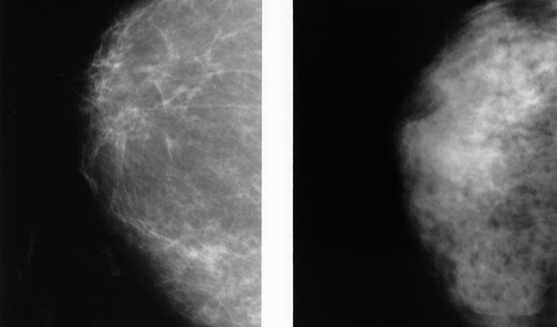

치밀 유방이란

유선 및 섬유 조직의 비율이 높고 지방 조직이 적은 유방을 말하는데, 한국인에게는 약 70%로 흔하다고 알려져 있습니다.

치밀 유방의 경우 작은 종양을 숨길 수 있기 때문에

기본으로 시행하는 유방촬영술에서 유방암을 발견하기 어렵게 만들 수 있습니다.

아시아 여성의 치밀 유방 발생률이 높기 때문에 유방 초음파는 유방암을 발견하는 데 중요한 검사입니다.

대만에서 실시된 한 연구에서 연구원들은 치밀 유방을 가진 여성의 유방암을 발견하는 데 유방 초음파가 유방 촬영술보다 더 민감하다는 것을 발견했습니다.

또한 유방 조영술에 유방 초음파를 추가하면 치밀 유방을 가진 여성의 유방암 발견율이 높아진다는 것을 발견했습니다.

연구에 따르면 유방 초음파는 기본 검사인 유방촬영술에서 보이지 않는 작은 유방암, 특히 치밀한 유방 조직을 가진 여성의 경우 발견되지 않았던 이상 병변을 발견할 수 있습니다.

따라서 치밀유방을 가진 여성의 경우 유방촬영술과 함께 유방 초음파검사를 시행하는 경우가 많습니다.